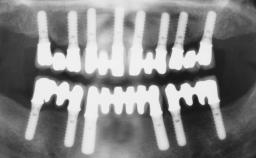

Iliac-Crest Block for Vertical and Horizontal Space Filling in the Anterior Maxilla

A 31-year-old man presented to our clinic 30 days after a motor vehicle accident in which he had suffered a dentoalveolar fracture in the anterior maxilla, including avulsion of teeth 12 and 11 and luxation of tooth 21. He was first treated on the night of the accident in a small city hospital with no oral and maxillofacial surgeon on the staff. A wired retention had been applied and the teeth repositioned to the best of the clinicians’ abilities. When he first presented to our care, the patient showed extrusion of teeth 12 and 11 associated with gingival recession due to bone loss in the anterior maxilla, and the stainless steel wires were still present.

# of Implants | 3 |

Bone Augmentation | Horizontal|Staged|Vertical |

Augmentation Materials | Autogenous chips|Autogenous block(s) |